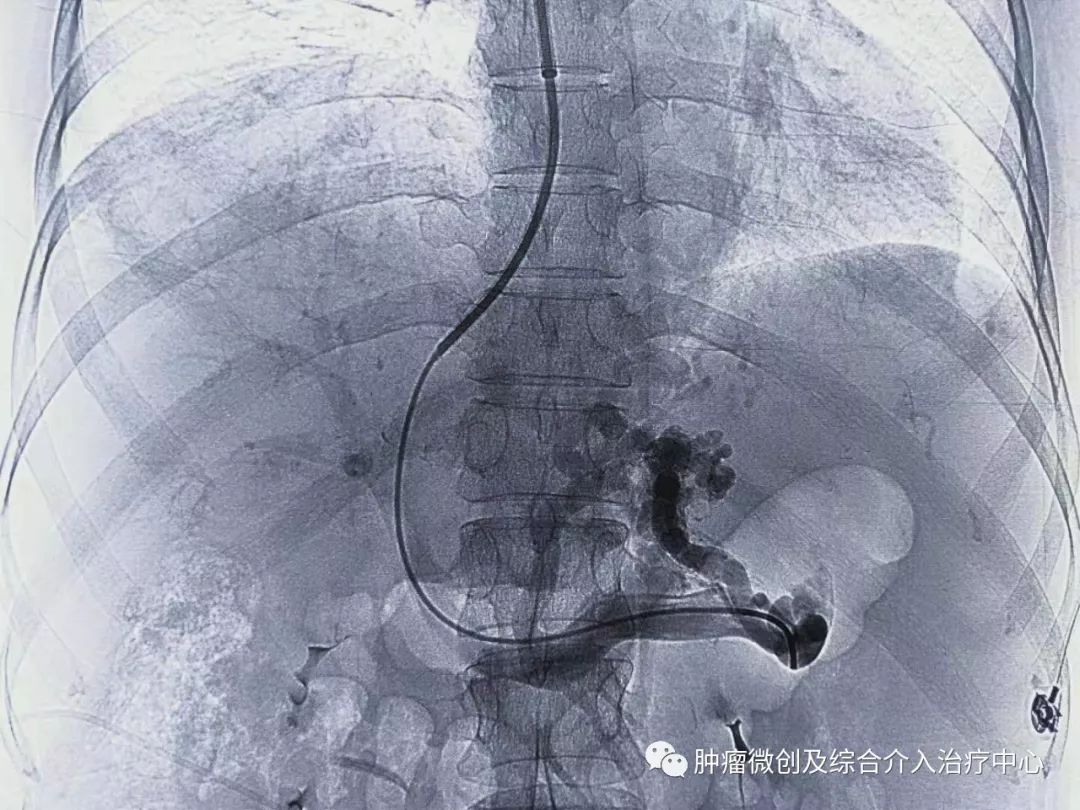

栓塞消化道出血责任血管:

再次造影可见:门脉血流流向-体静脉达到分流目的,术前侧压力42,术后25,门脉压力明显降低,达到防止再次出血目的。